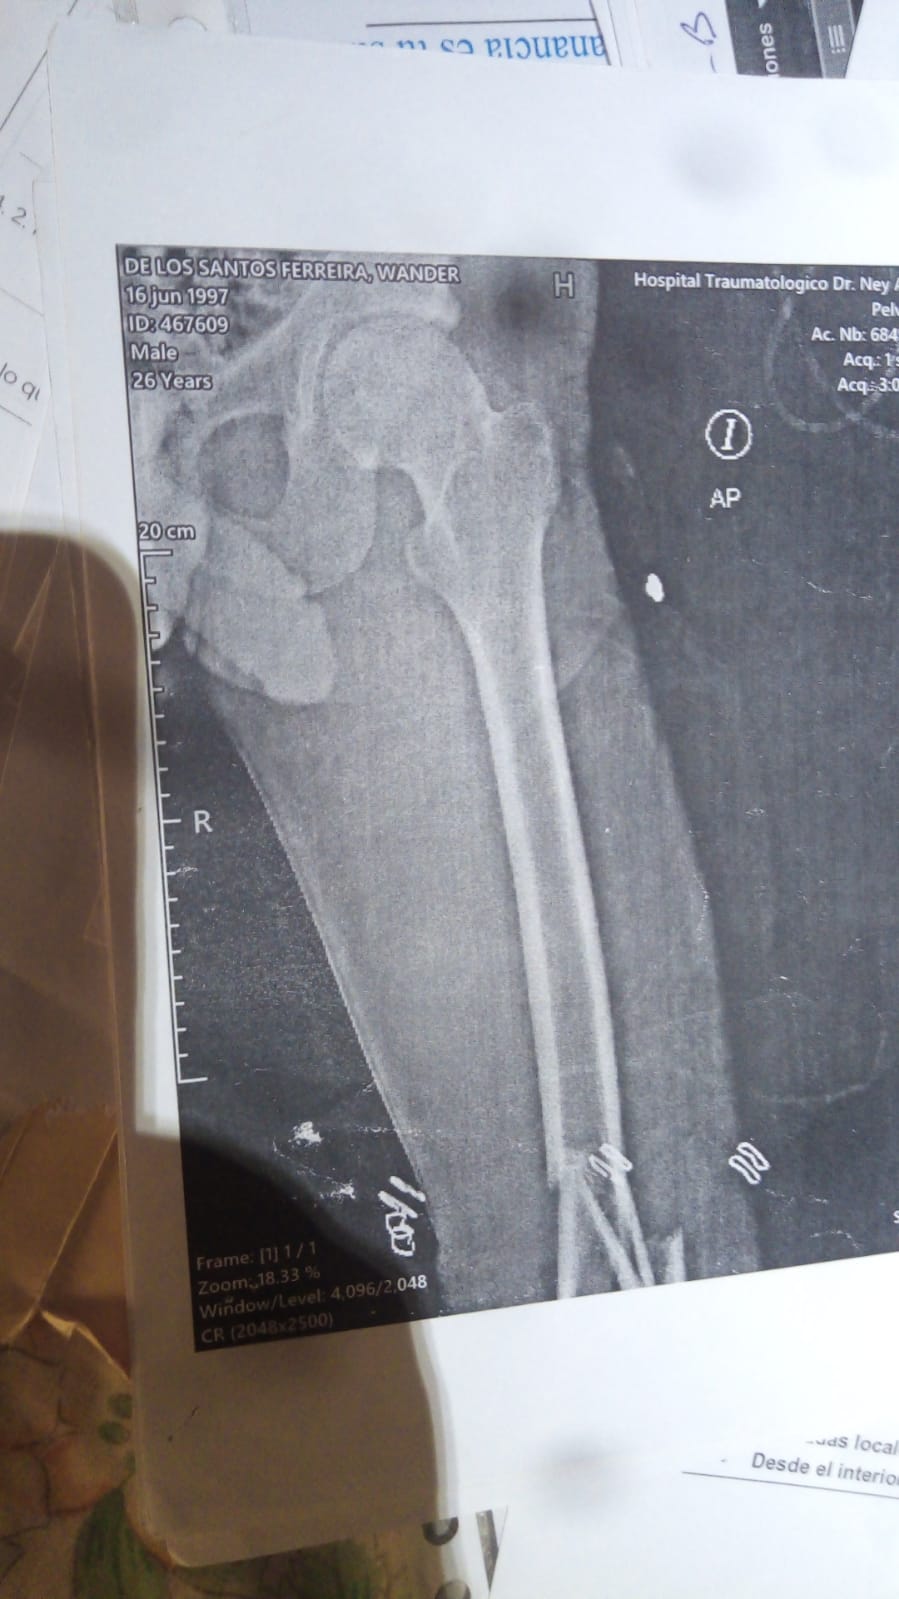

Santo Domingo.– SANTO DOMINGO.- Una mujer denunció, a través del WhatsApp de Noticias SIN, que un hombre agredió de manera brusca a su hijo, rompiéndole las piernas por una supuesta deuda de 600 pesos, en un hecho ocurrido en el mes de septiembre, en el sector los Trinitarios Segundo en la Charles de Gaulle.

“Esa persona agredió físicamente a mi hijo por una deuda de 600 pesos, con un bate lo atacó de espalda, le rompió las dos piernas “, dijo denunciante.

Se trata de Antoni Batista, quien le ataco a Wander de los santos Ferrera, y se dio a la fuga cuando cometió el hecho.